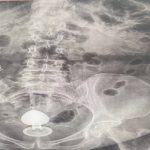

O caso foi atendido pelo cirurgião coloproctologista Daniel Brosco. Segundo o médico, a paciente contou que, na verdade, estava usando o sex toy para ajudar com a constipação intestinal, e não com finalidade sexual. O médico alerta que isso é contraindicado.

O médico explica que a paciente tinha um quadro de pólipos no intestino — quando a mucosa apresenta um crescimento anormal que pode evoluir para câncer. Com isso, a parede intestinal era mais sensível, aumentando o risco de perfuração.

Brosco afirma que ela passou pelo procedimento para retirada do objeto e passa bem, mas que o caso é um alerta sobre o uso desse tipo de brinquedo. O uso inadequado pode levar a complicações como lacerações, sangramentos e perfurações intestinais — especialmente em pacientes com condições prévias que tornam a mucosa mais sensível.